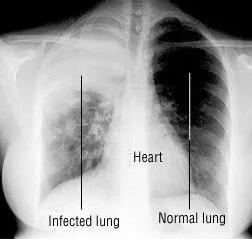

Lung Vision: X-ray-based Classification of Pulmonary Diseases

Prepared a dataset containing Normal, Tuberculosis (TB), and Pneumonia lung X-rays, and implemented a Deep Neural Network (DNN) to accurately classify these three categories. The challenge was to tackle the class imbalance inherent in the dataset.